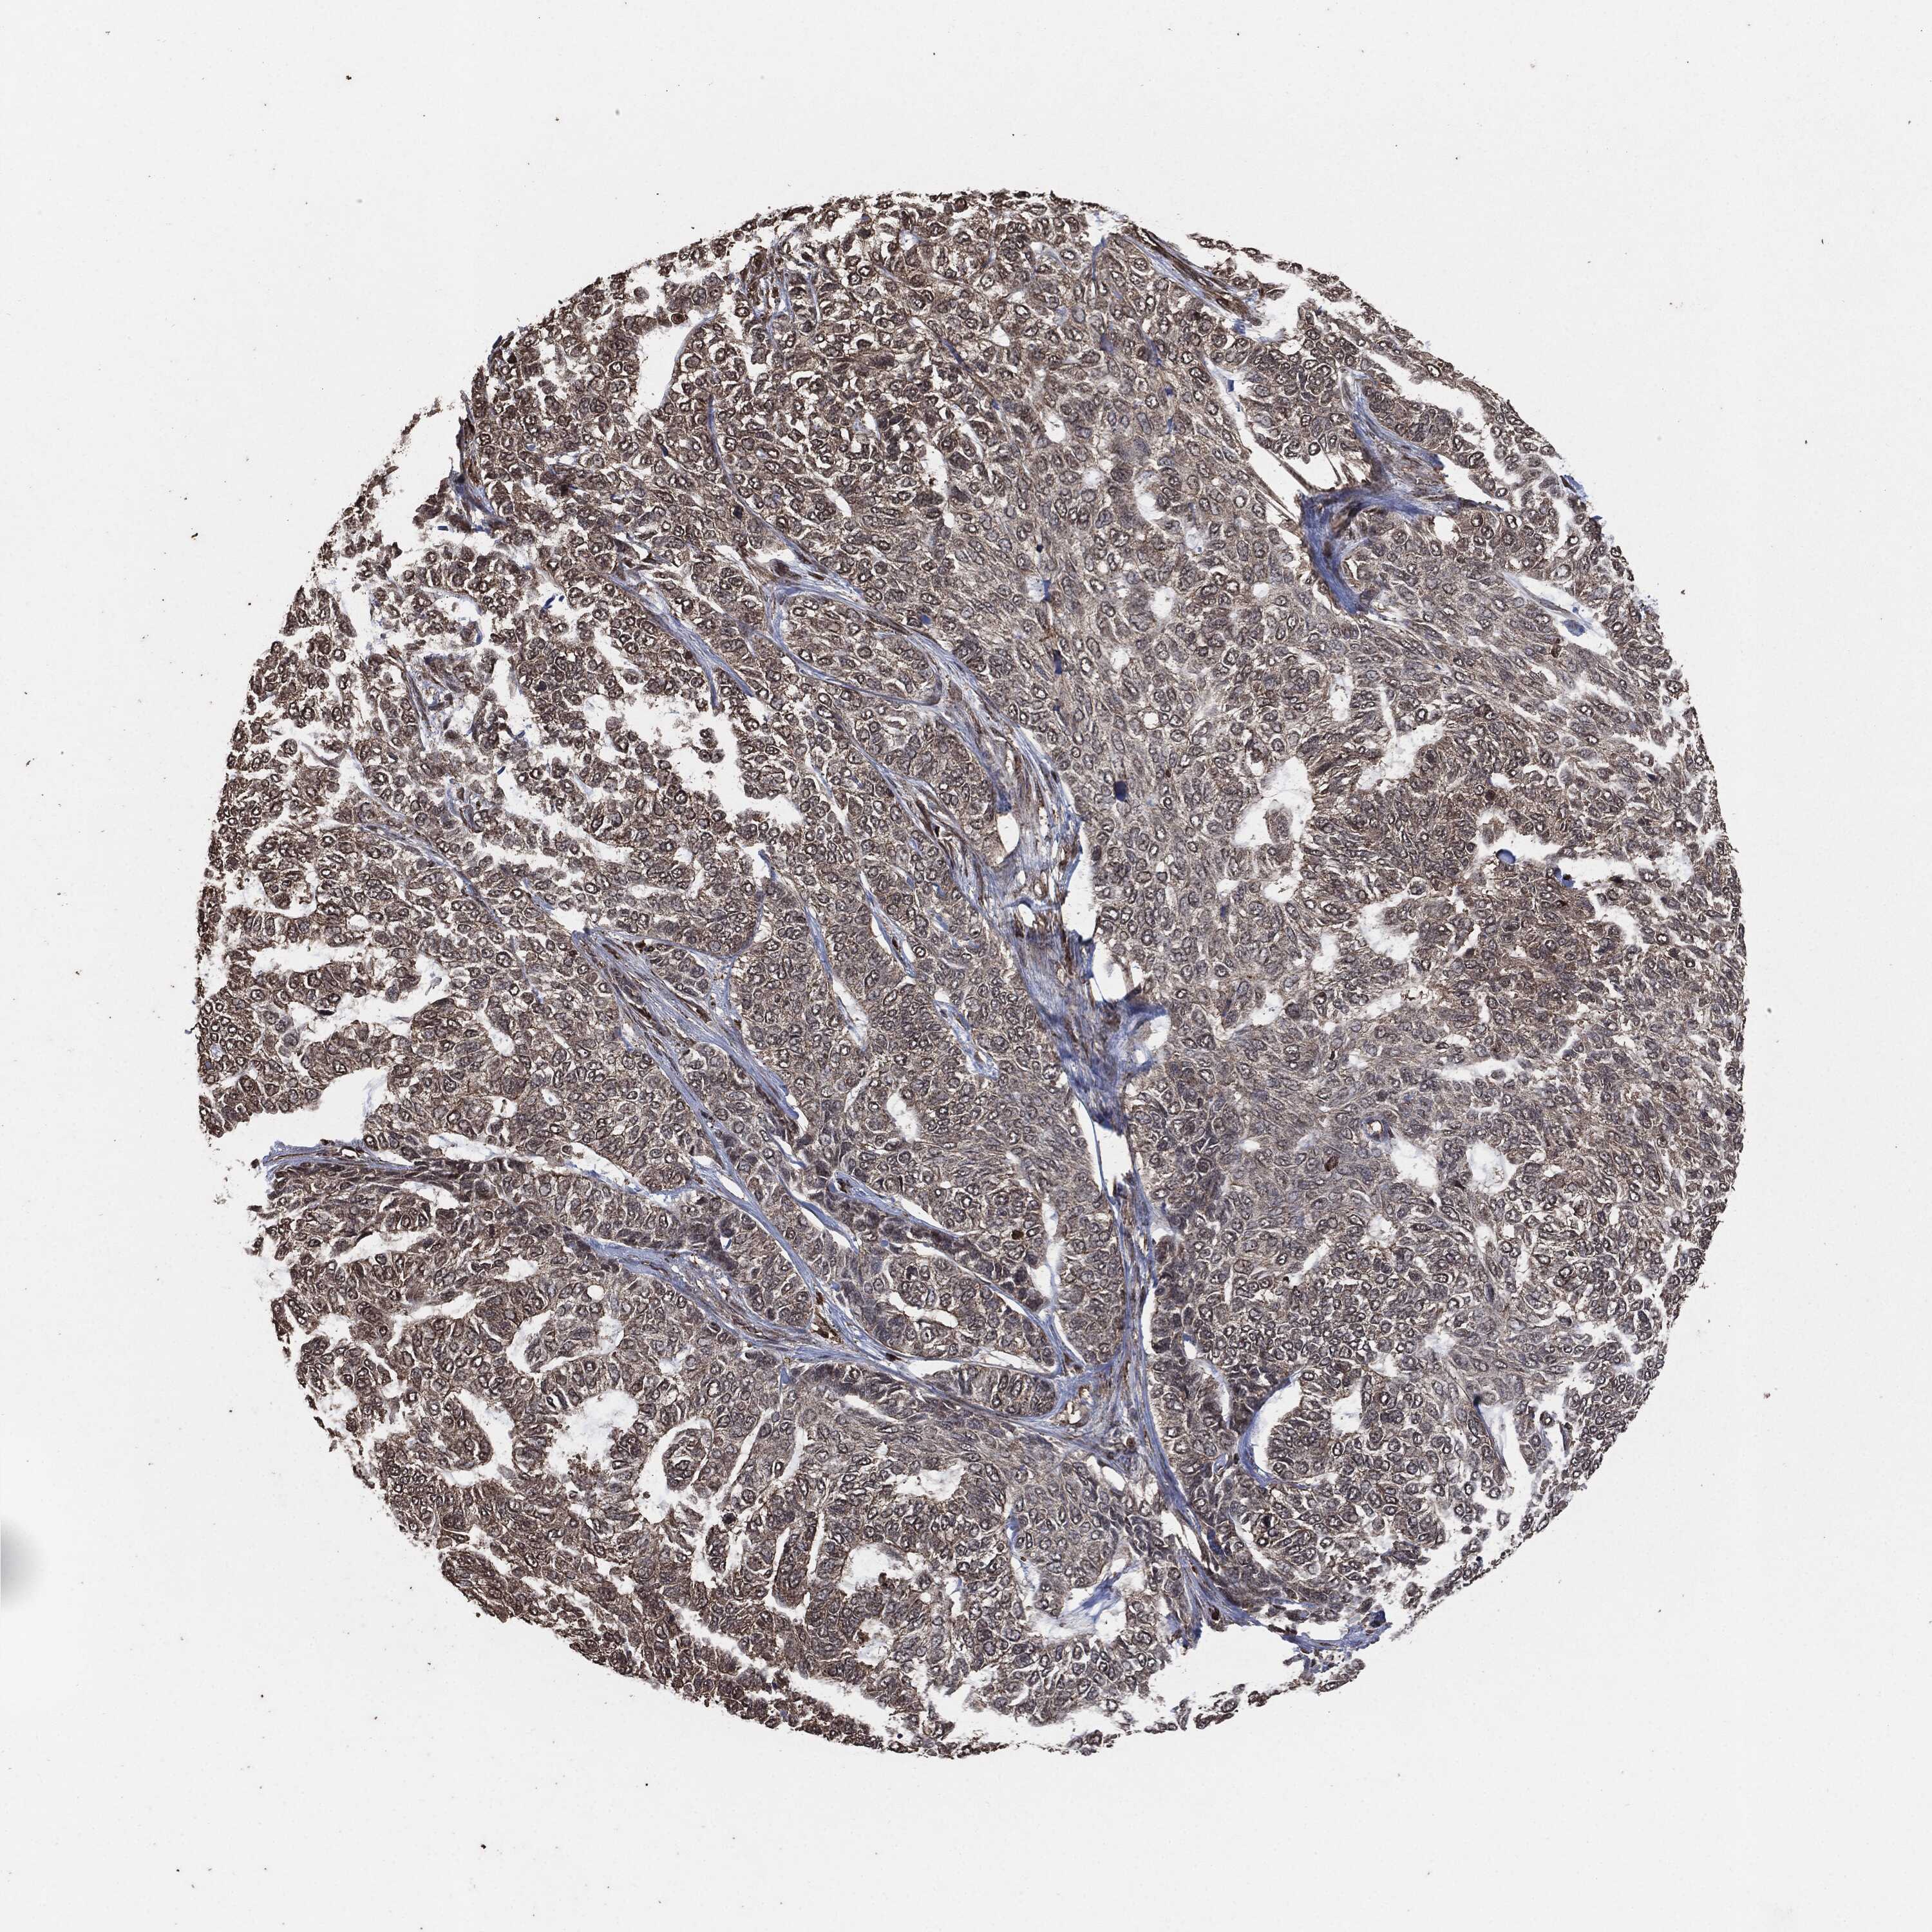

SKIN CANCER - Protein expressioni

A mouse-over function shows sample information and annotation data. Click on an image to view it in a full screen mode. Samples can be filtered based on level of antibody staining by selecting one or several of the following categories: high, medium, low and not detected. The assay and annotation is described here.

Antibody stainingi

Antibody staining in the annotated cell types in the current human tissue is reported as not detected, low, medium, or high, based on conventional immunohistochemistry profiling in selected tissues. This score is based on the combination of the staining intensity and fraction of stained cells.

Each image is clickable and will lead to virtual microscopy that enables deeper exploration of all samples and also displays staining intensity scores, fraction scores and subcellular localization as well as patient and tissue information for each sample.

Squamous cell carcinoma, NOS

Basal cell carcinoma

Squamous cell carcinoma in situ, NOS

Squamous cell carcinoma, metastatic, NOS